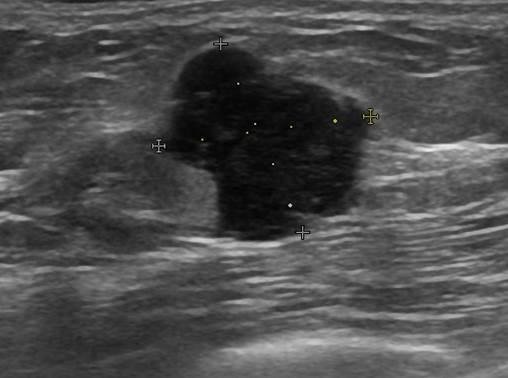

Ung thư vú

Ung thư vú - Ảnh 2

Ung thư vú - Ảnh 3

Ung thư vú - Ảnh 4

» Thông tin: Nữ giới – 55 tuổi.

» Lâm sàng: Khối tuyến vú.